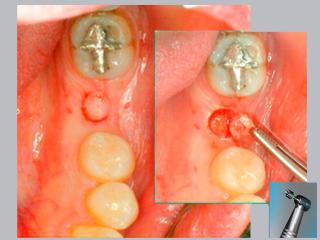

En este sentido nuestro consultorio desarrolla desde 1999 la técnica flapless prescindiendo del bisturí convencional y sin sutura, a través de una incisión circular de 5 mm de diámetro que garantiza un postoperatorio que pasa inadvertido y logra excelente resultado estético.

La técnica quirúrgica flapless (sin solapa) posee varias ventajas comparada con los procedimientos quirúrgicos convencionales, que incluyen la apertura de una solapa (flap) antes de la inserción del implante.